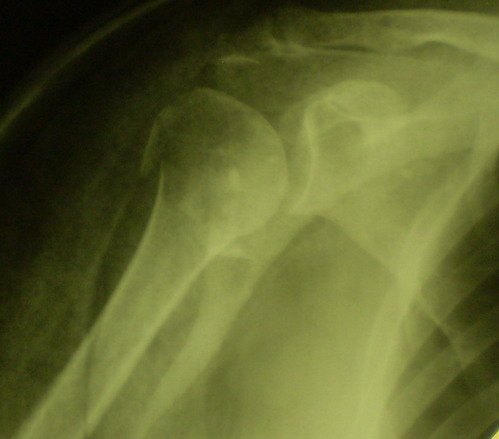

[Ortho] Оскольчатый перелом шейки, головки плечевой кости

Снимки на 1-е сутки после репозиции и на 8- сутки после репозиции.

Имя     : repozitcia, 1-e sutki.jpg

Имя     : repozitcia, 8-e sutki.jpg